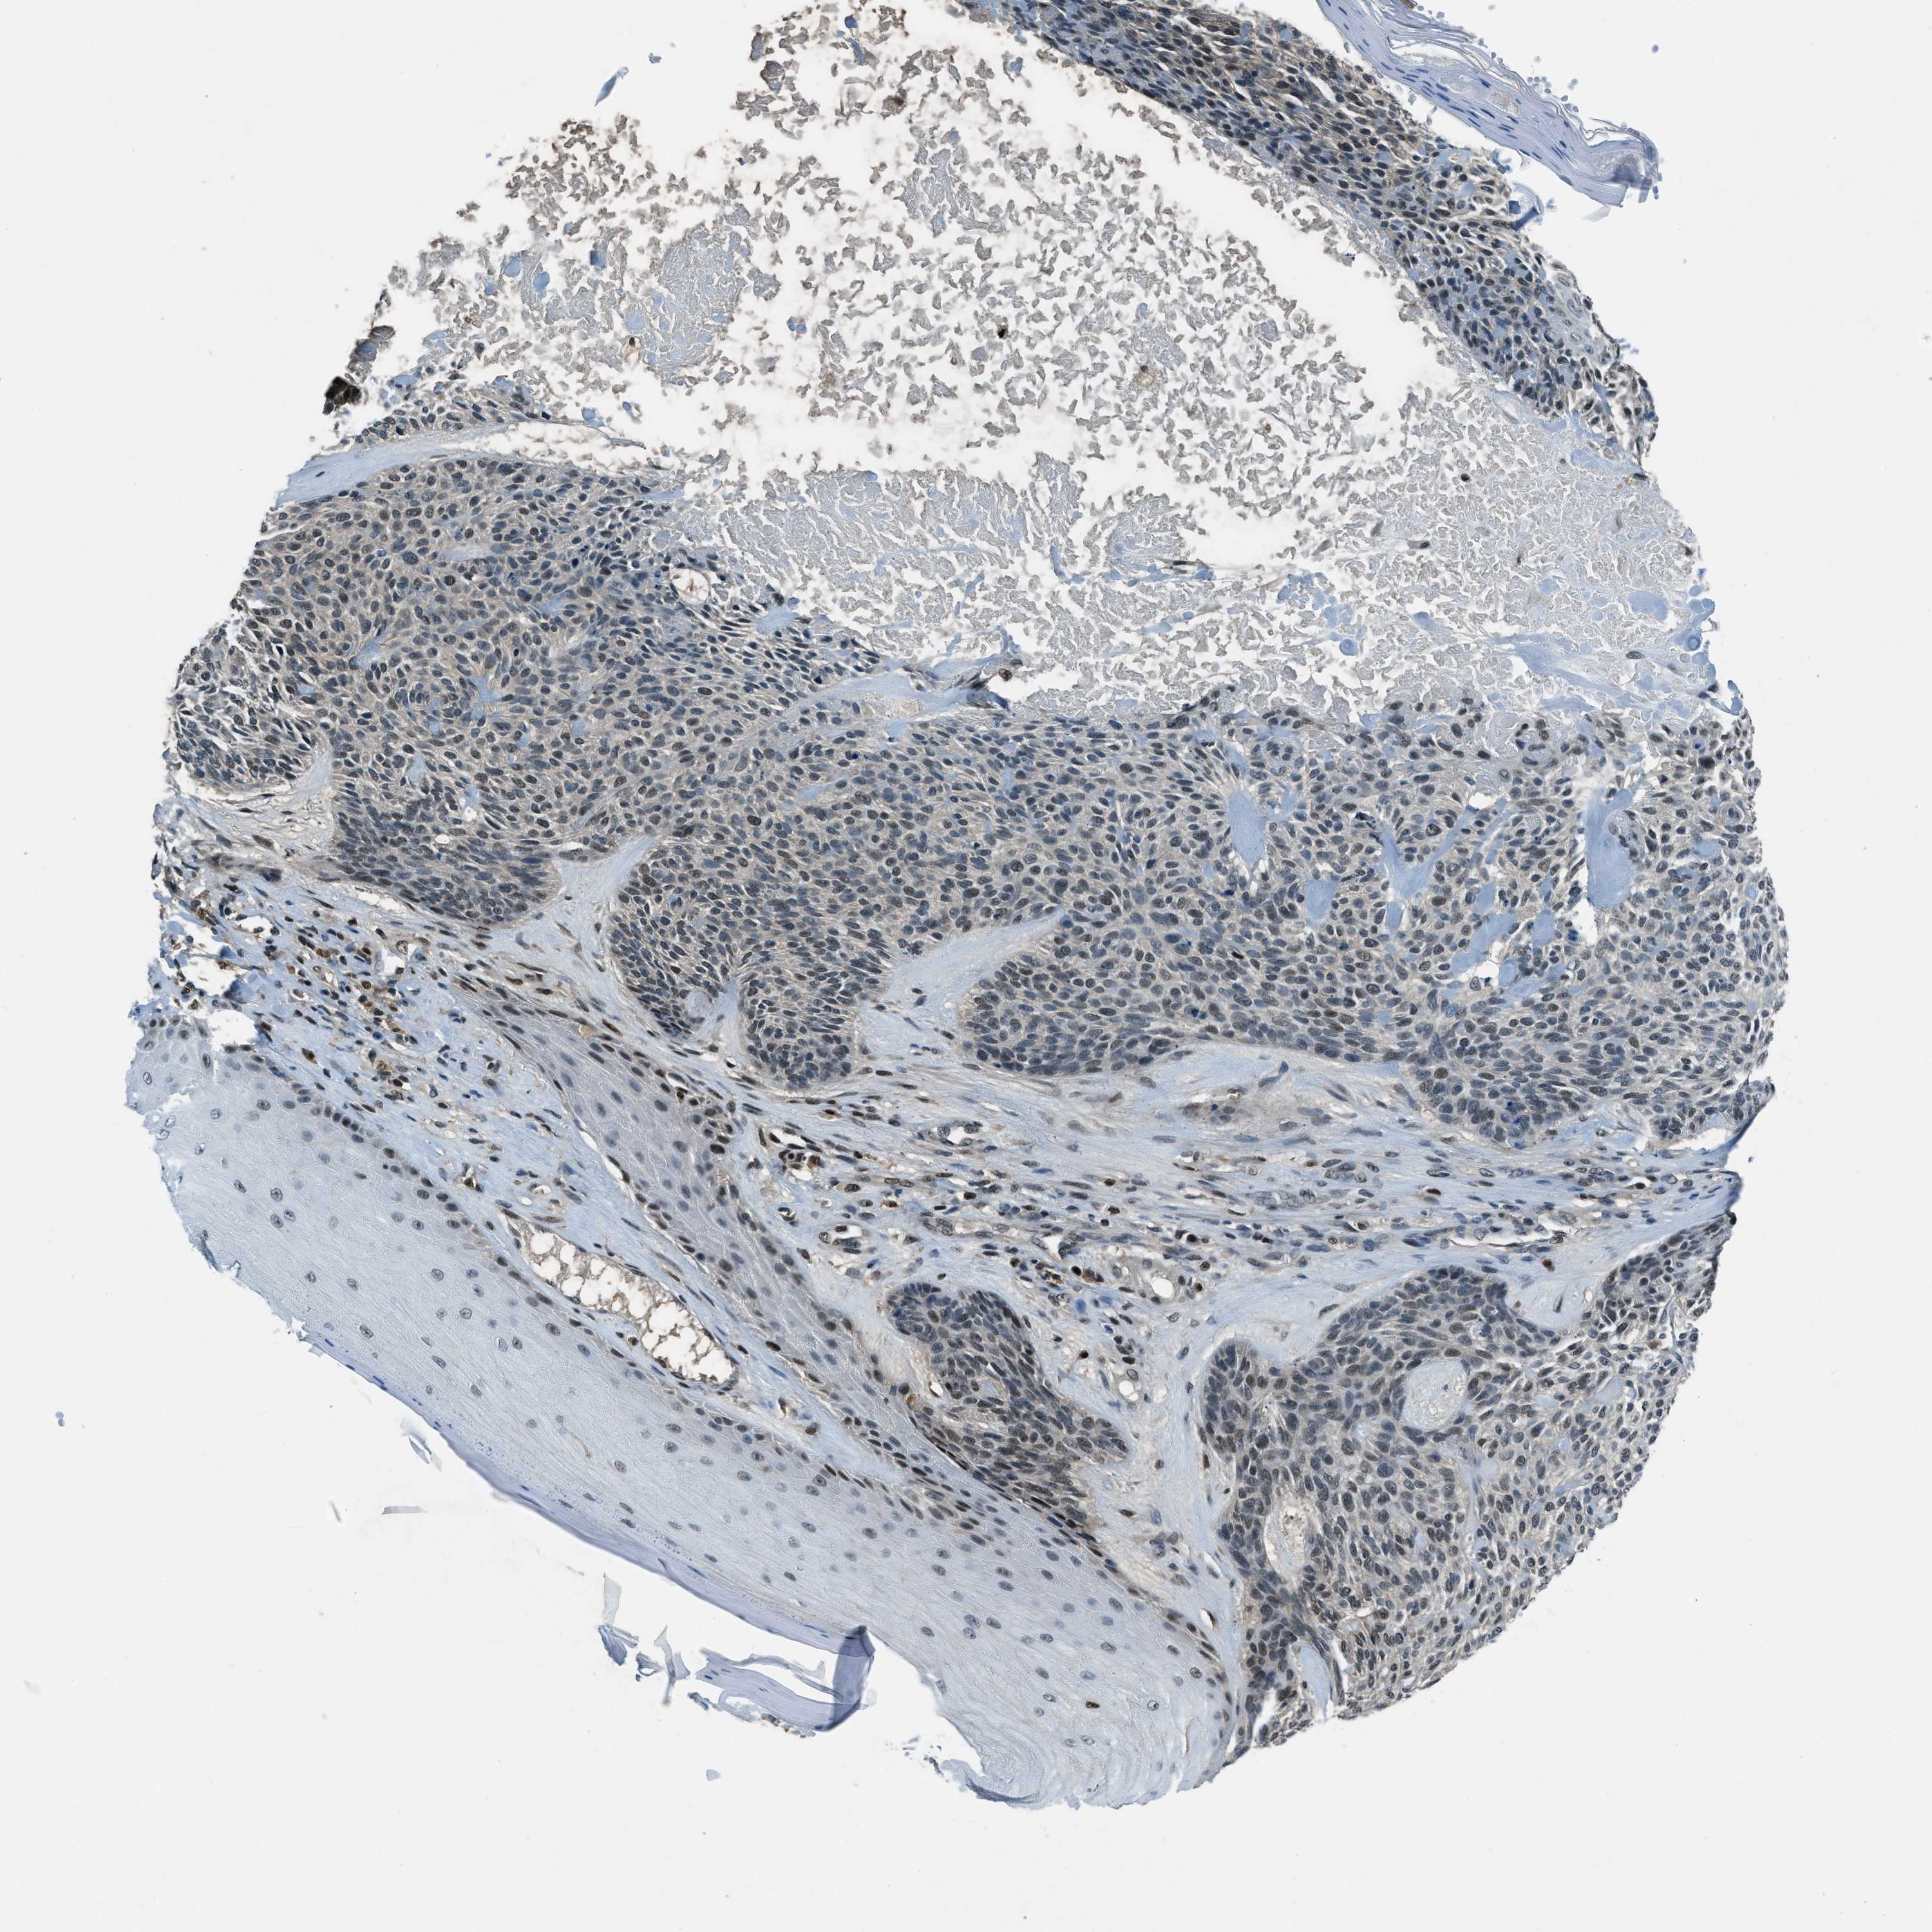

SKIN CANCER - Protein expressioni

A mouse-over function shows sample information and annotation data. Click on an image to view it in a full screen mode. Samples can be filtered based on level of antibody staining by selecting one or several of the following categories: high, medium, low and not detected. The assay and annotation is described here.

Each image is clickable and will lead to virtual microscopy that enables deeper exploration of all samples and also displays staining intensity scores, fraction scores and subcellular localization as well as patient and tissue information for each sample.

Antibody HPA017899

Staining

High

Intensity

Strong

Quantity

>75%

Location

Nuclear

Basal cell carcinoma